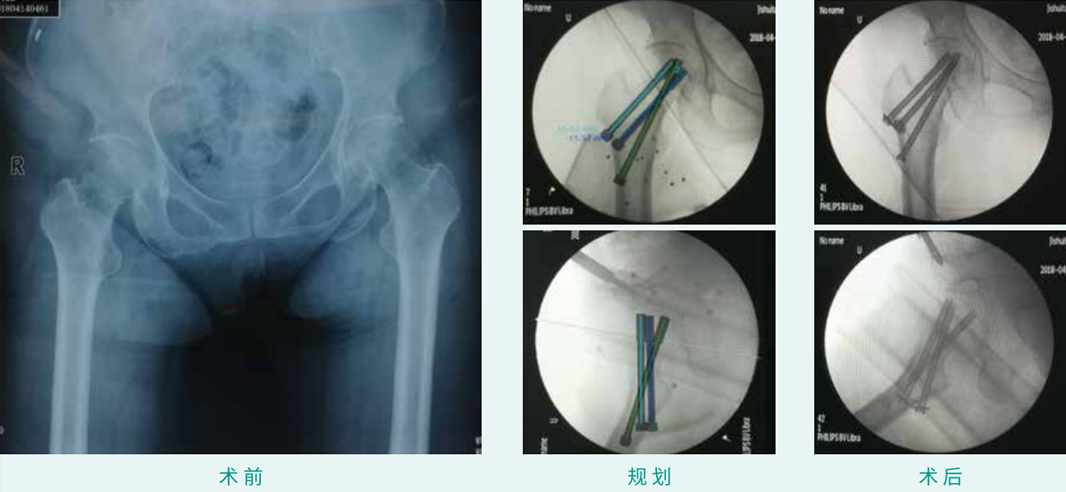

天玑? 辅助股骨颈BDSF经皮空心螺钉内牢靠术

基本情形:患者女,,,,,,,,63岁,,,,,,,,股骨颈骨折

机械人累积用时:10分钟

植入物:3枚空心螺钉

病例泉源:北京积水潭医院 王军强